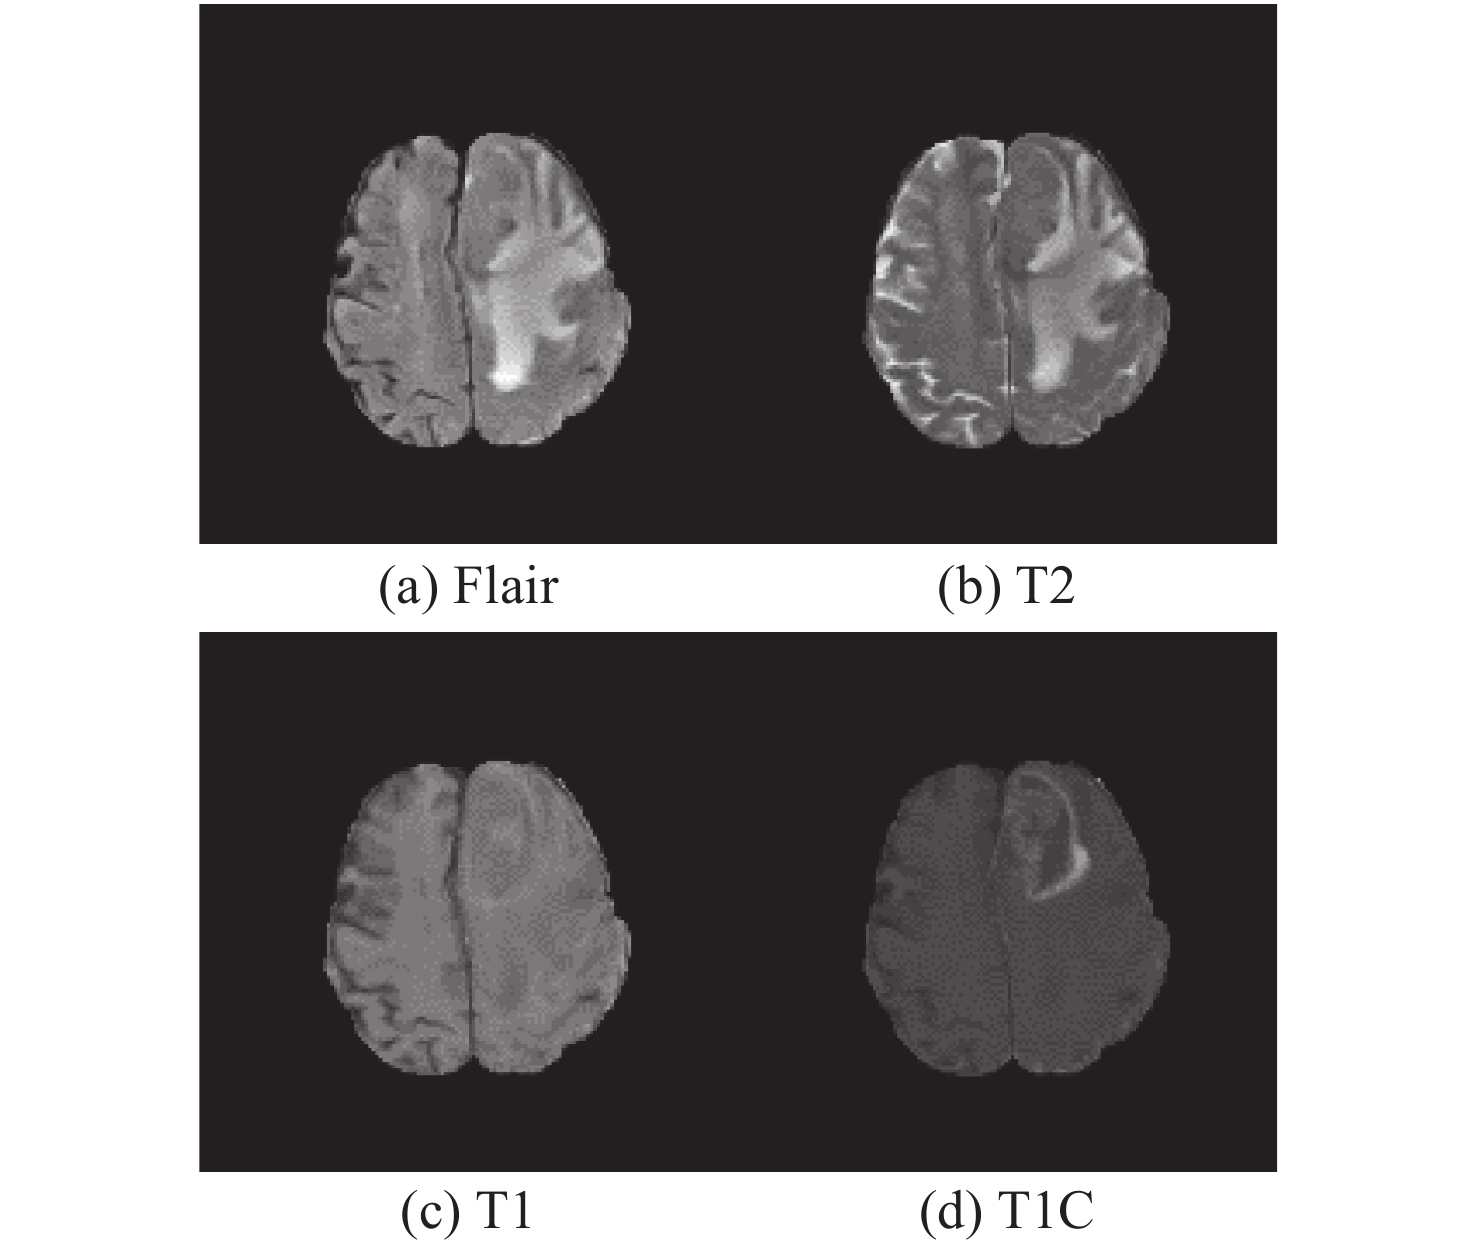

Classification model based on fusion of multi-scale feature and channel feature for benign and malignant brain tumors

JIANG Lin-qi, NING Chun-yu, YU Hai-tao

2022, 15(6): 1339-1349. doi: 10.37188/CO.2022-0067

Abstract:

Aiming at the problems of complex and inaccurate classification of benign and malignant brain tumors, a classification model was proposed based on the fusion of multi-scale and channel features. The model used ResNeXt as the backbone network. First, the multi-scale feature extraction module based on dilated convolution was used to replace the first convolution layer, which can make full use of dilation rates to obtain the image information from different receptive fields, and combine the global features with significant subtle ones. Second, the channel attention mechanism module was added in the network to fuse the feature channel information in order to increase the attention to the tumor, and reduce the attention to redundant information. Finally, the combination optimization strategy, the MultiStepLR strategy of the learning rate, the label smoothing strategy and the transfer learning strategy on medical images were adopted to improve the learning and generalization abilities of the model. The experiments were carried out on BraTS2017 Dataset and BraTS2019 Dataset, and the classification accuracy were 98.11% and 98.72%, respectively. Compared with other advanced methods and classical models, the proposed classification model can effectively reduce the complexity of the classification process and improve the detection accuracy of benign and malignant brain tumors.